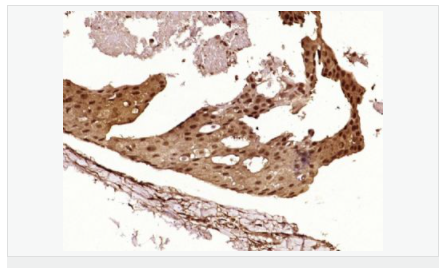

| 產品應用 | WB=1:500-2000 ELISA=1:5000-10000 IHC-P=1:100-500 IHC-F=1:100-500 Flow-Cyt=1μg/Test ICC=1:100 IF=1:100-500 (石蠟切片需做抗原修復) not yet tested in other applications. optimal dilutions/concentrations should be determined by the end user. |

| 細胞定位 | 細胞核 細胞漿 |

| 產品介紹 | This gene encodes a tumor suppressor protein containing transcriptional activation, DNA binding, and oligomerization domains. The encoded protein responds to diverse cellular stresses to regulate expression of target genes, thereby inducing cell cycle arrest, apoptosis, senescence, DNA repair, or changes in metabolism. Mutations in this gene are associated with a variety of human cancers, including hereditary cancers such as Li-Fraumeni syndrome. Alternative splicing of this gene and the use of alternate promoters result in multiple transcript variants and isoforms. Additional isoforms have also been shown to result from the use of alternate translation initiation codons (PMIDs: 12032546, 20937277). [provided by RefSeq, Feb 2013]. Function: Acts as a tumor suppressor in many tumor types; induces growth arrest or apoptosis depending on the physiological circumstances and cell type. Involved in cell cycle regulation as a trans-activator that acts to negatively regulate cell division by controlling a set of genes required for this process. One of the activated genes is an inhibitor of cyclin-dependent kinases. Apoptosis induction seems to be mediated either by stimulation of BAX and FAS antigen expression, or by repression of Bcl-2 expression. Implicated in Notch signaling cross-over. Prevents CDK7 kinase activity when associated to CAK complex in response to DNA damage, thus stopping cell cycle progression. Isoform 2 enhances the transactivation activity of isoform 1 from some but not all TP53-inducible promoters. Isoform 4 suppresses transactivation activity and impairs growth suppression mediated by isoform 1. Isoform 7 inhibits isoform 1-mediated apoptosis. Subunit: Interacts with AXIN1. Probably part of a complex consisting of TP53, HIPK2 and AXIN1 (By similarity). Binds DNA as a homotetramer. Interacts with histone acetyltransferases EP300 and methyltransferases HRMT1L2 and CARM1, and recruits them to promoters. In vitro, the interaction of TP53 with cancer-associated/HPV (E6) viral proteins leads to ubiquitination and degradation of TP53 giving a possible model for cell growth regulation. This complex formation requires an additional factor, E6-AP, which stably associates with TP53 in the presence of E6. Interacts (via C-terminus) with TAF1; when TAF1 is part of the TFIID complex. Interacts with ING4; this interaction may be indirect. Found in a complex with CABLES1 and TP73. Interacts with HIPK1, HIPK2, and TP53INP1. Interacts with WWOX. May interact with HCV core protein. Interacts with USP7 and SYVN1. Interacts with HSP90AB1. Interacts with CHD8; leading to recruit histone H1 and prevent transactivation activity (By similarity). Interacts with ARMC10, BANP, CDKN2AIP, NUAK1, STK11/LKB1, UHRF2 and E4F1. Interacts with YWHAZ; the interaction enhances TP53 transcriptional activity. Phosphorylation of YWHAZ on 'Ser-58' inhibits this interaction. Interacts (via DNA-binding domain) with MAML1 (via N-terminus). Interacts with MKRN1. Interacts with PML (via C-terminus). Interacts with MDM2; leading to ubiquitination and proteasomal degradation of TP53. Directly interacts with FBXO42; leading to ubiquitination and degradation of TP53. Interacts (phosphorylated at Ser-15 by ATM) with the phosphatase PP2A-PPP2R5C holoenzyme; regulates stress-induced TP53-dependent inhibition of cell proliferation. Interacts with PPP2R2A. Interacts with AURKA, DAXX, BRD7 and TRIM24. Interacts (when monomethylated at Lys-382) with L3MBTL1. Isoform 1 interacts with isoform 2 and with isoform 4. Interacts with GRK5. Binds to the CAK complex (CDK7, cyclin H and MAT1) in response to DNA damage. Interacts with CDK5 in neurons. Interacts with AURKB, UHRF2 and NOC2L. Interacts (via N-terminus) with PTK2/FAK1; this promotes ubiquitination by MDM2. Interacts with PTK2B/PYK2; this promotes ubiquitination by MDM2. Interacts with PRKCG. Interacts with human cytomegalovirus/HHV-5 protein UL123. Subcellular Location: Cytoplasm. Nucleus. Nucleus, PML body. Endoplasmic reticulum. Note=Interaction with BANP promotes nuclear localization. Recruited into PML bodies together with CHEK2. Isoform 1: Nucleus. Cytoplasm. Note=Predominantly nuclear but localizes to the cytoplasm when expressed with isoform 4. Isoform 2: Nucleus. Cytoplasm. Note=Localized mainly in the nucleus with minor staining in the cytoplasm. Isoform 3: Nucleus. Cytoplasm. Note=Localized in the nucleus in most cells but found in the cytoplasm in some cells. Isoform 4: Nucleus. Cytoplasm. Note=Predominantly nuclear but translocates to the cytoplasm following cell stress. Isoform 7: Nucleus. Cytoplasm. Note=Localized mainly in the nucleus with minor staining in the cytoplasm. Isoform 8: Nucleus. Cytoplasm. Note=Localized in both nucleus and cytoplasm in most cells. In some cells, forms foci in the nucleus that are different from nucleoli. Isoform 9: Cytoplasm. Tissue Specificity: Ubiquitous. Isoforms are expressed in a wide range of normal tissues but in a tissue-dependent manner. Isoform 2 is expressed in most normal tissues but is not detected in brain, lung, prostate, muscle, fetal brain, spinal cord and fetal liver. Isoform 3 is expressed in most normal tissues but is not detected in lung, spleen, testis, fetal brain, spinal cord and fetal liver. Isoform 7 is expressed in most normal tissues but is not detected in prostate, uterus, skeletal muscle and breast. Isoform 8 is detected only in colon, bone marrow, testis, fetal brain and intestine. Isoform 9 is expressed in most normal tissues but is not detected in brain, heart, lung, fetal liver, salivary gland, breast or intestine. Post-translational modifications: Acetylated. Acetylation of Lys-382 by CREBBP enhances transcriptional activity. Deacetylation of Lys-382 by SIRT1 impairs its ability to induce proapoptotic program and modulate cell senescence. Phosphorylation on Ser residues mediates transcriptional activation. Phosphorylated by HIPK1. Phosphorylation at Ser-9 by HIPK4 increases repression activity on BIRC5 promoter. Phosphorylated on Thr-18 by VRK1. Phosphorylated on Ser-20 by CHEK2 in response to DNA damage, which prevents ubiquitination by MDM2. Phosphorylated on Ser-20 by PLK3 in response to reactive oxygen species (ROS), promoting p53/TP53-mediated apoptosis. Phosphorylated on Thr-55 by TAF1, which promotes MDM2-mediated degradation. Phosphorylated on Ser-33 by CDK7 in a CAK complex in response to DNA damage. Phosphorylated on Ser-46 by HIPK2 upon UV irradiation. Phosphorylation on Ser-46 is required for acetylation by CREBBP. Phosphorylated on Ser-392 following UV but not gamma irradiation. Phosphorylated upon DNA damage, probably by ATM or ATR. Phosphorylated on Ser-15 upon ultraviolet irradiation; which is enhanced by interaction with BANP. Phosphorylated by NUAK1 at Ser-15 and Ser-392; was initially thought to be mediated by STK11/LKB1 but it was later shown that it is indirect and that STK11/LKB1-dependent phosphorylation is probably mediated by downstream NUAK1 (PubMed:21317932). It is unclear whether AMP directly mediates phosphorylation at Ser-15. Phosphorylated on Thr-18 by isoform 1 and isoform 2 of VRK2. Phosphorylation on Thr-18 by isoform 2 of VRK2 results in a reduction in ubiquitination by MDM2 and an increase in acetylation by EP300. Stabilized by CDK5-mediated phosphorylation in response to genotoxic and oxidative stresses at Ser-15, Ser-33 and Ser-46, leading to accumulation of p53/TP53, particularly in the nucleus, thus inducing the transactivation of p53/TP53 target genes. Phosphorylated at Ser-315 and Ser-392 by CDK2 in response to DNA-damage. Dephosphorylated by PP2A-PPP2R5C holoenzyme at Thr-55. SV40 small T antigen inhibits the dephosphorylation by the AC form of PP2A. May be O-glycosylated in the C-terminal basic region. Studied in EB-1 cell line. Ubiquitinated by MDM2 and SYVN1, which leads to proteasomal degradation. Ubiquitinated by RFWD3, which works in cooperation with MDM2 and may catalyze the formation of short polyubiquitin chains on p53/TP53 that are not targeted to the proteasome. Ubiquitinated by MKRN1 at Lys-291 and Lys-292, which leads to proteasomal degradation. Deubiquitinated by USP10, leading to its stabilization. Ubiquitinated by TRIM24, which leads to proteasomal degradation. Ubiquitination by TOPORS induces degradation. Deubiquitination by USP7, leading to stabilization. Isoform 4 is monoubiquitinated in an MDM2-independent manner. Monomethylated at Lys-372 by SETD7, leading to stabilization and increased transcriptional activation. Monomethylated at Lys-370 by SMYD2, leading to decreased DNA-binding activity and subsequent transcriptional regulation activity. Lys-372 monomethylation prevents interaction with SMYD2 and subsequent monomethylation at Lys-370. Dimethylated at Lys-373 by EHMT1 and EHMT2. Monomethylated at Lys-382 by SETD8, promoting interaction with L3MBTL1 and leading to repress transcriptional activity. Demethylation of dimethylated Lys-370 by KDM1A prevents interaction with TP53BP1 and represses TP53-mediated transcriptional activation. Sumoylated by SUMO1. DISEASE: Note=TP53 is found in increased amounts in a wide variety of transformed cells. TP53 is frequently mutated or inactivated in about 60% of cancers. TP53 defects are found in Barrett metaplasia a condition in which the normally stratified squamous epithelium of the lower esophagus is replaced by a metaplastic columnar epithelium. The condition develops as a complication in approximately 10% of patients with chronic gastroesophageal reflux disease and predisposes to the development of esophageal adenocarcinoma. Defects in TP53 are a cause of esophageal cancer (ESCR) [MIM:133239]. Defects in TP53 are a cause of Li-Fraumeni syndrome (LFS) [MIM:151623]. LFS is an autosomal dominant familial cancer syndrome that in its classic form is defined by the existence of a proband affected by a sarcoma before 45 years with a first degree relative affected by any tumor before 45 years and another first degree relative with any tumor before 45 years or a sarcoma at any age. Other clinical definitions for LFS have been proposed (PubMed:8118819 and PubMed:8718514) and called Li-Fraumeni like syndrome (LFL). In these families affected relatives develop a diverse set of malignancies at unusually early ages. Four types of cancers account for 80% of tumors occurring in TP53 germline mutation carriers: breast cancers, soft tissue and bone sarcomas, brain tumors (astrocytomas) and adrenocortical carcinomas. Less frequent tumors include choroid plexus carcinoma or papilloma before the age of 15, rhabdomyosarcoma before the age of 5, leukemia, Wilms tumor, malignant phyllodes tumor, colorectal and gastric cancers. Defects in TP53 are involved in head and neck squamous cell carcinomas (HNSCC) Defects in TP53 are a cause of lung cancer (LNCR) [MIM:211980]. LNCR is a common malignancy affecting tissues of the lung. The most common form of lung cancer is non-small cell lung cancer (NSCLC) that can be divided into 3 major histologic subtypes: squamous cell carcinoma, adenocarcinoma, and large cell lung cancer. NSCLC is often diagnosed at an advanced stage and has a poor prognosis. Defects in TP53 are a cause of choroid plexus papilloma (CPLPA) [MIM:260500]. Choroid plexus papilloma is a slow-growing benign tumor of the choroid plexus that often invades the leptomeninges. In children it is usually in a lateral ventricle but in adults it is more often in the fourth ventricle. Hydrocephalus is common, either from obstruction or from tumor secretion of cerebrospinal fluid. If it undergoes malignant transformation it is called a choroid plexus carcinoma. Primary choroid plexus tumors are rare and usually occur in early childhood. Defects in TP53 are a cause of adrenocortical carcinoma (ADCC) [MIM:202300]. ADCC is a rare childhood tumor of the adrenal cortex. It occurs with increased frequency in patients with the Beckwith-Wiedemann syndrome and is a component tumor in Li-Fraumeni yndrome. Similarity: Belongs to the p53 family. SWISS: P04637 Gene ID: 7157 Database links: Entrez Gene: 7157 Human Entrez Gene: 22059 Mouse Omim: 191170 Human SwissProt: P04637 Human SwissProt: P02340 Mouse Unigene: 654481 Human Unigene: 222 Mouse Unigene: 54443 Rat Important Note: This product as supplied is intended for research use only, not for use in human, therapeutic or diagnostic applications. wtp53廣泛的研究發現P53腫瘤抑制基因對50%以上的人類癌癥具有抑制突變的功能。P53蛋白水平在正常細胞中表達低,在DNA突變時或各種各樣細胞遇難信號時反應增加。該基因突變或缺失是導致許多腫瘤發生的原因。 野生型P53(wt-p53)可誘導細胞凋亡,并通過細胞凋亡抑制腫瘤生長,而P53的突變或缺失則可抑制野生型P53的功能,使得缺陷細胞得以存活下來,從而導致腫瘤發生。 P53同時也是細胞凋亡的調控因子。此抗體可用于P53腫瘤抑制基因功能的研究。 |